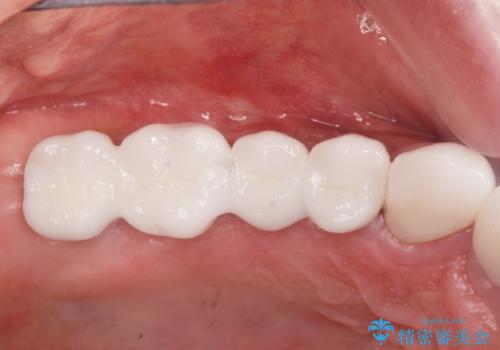

- 165万円(インプラント×3・チタンカスタムアバットメント×3・ジルコニアクラウン×4・仮歯×6)費用は治療当時の料金となります

長らく気になっていた歯ぐきの疼くような感じや、咬合機能が改善され、満足いただくことができました。